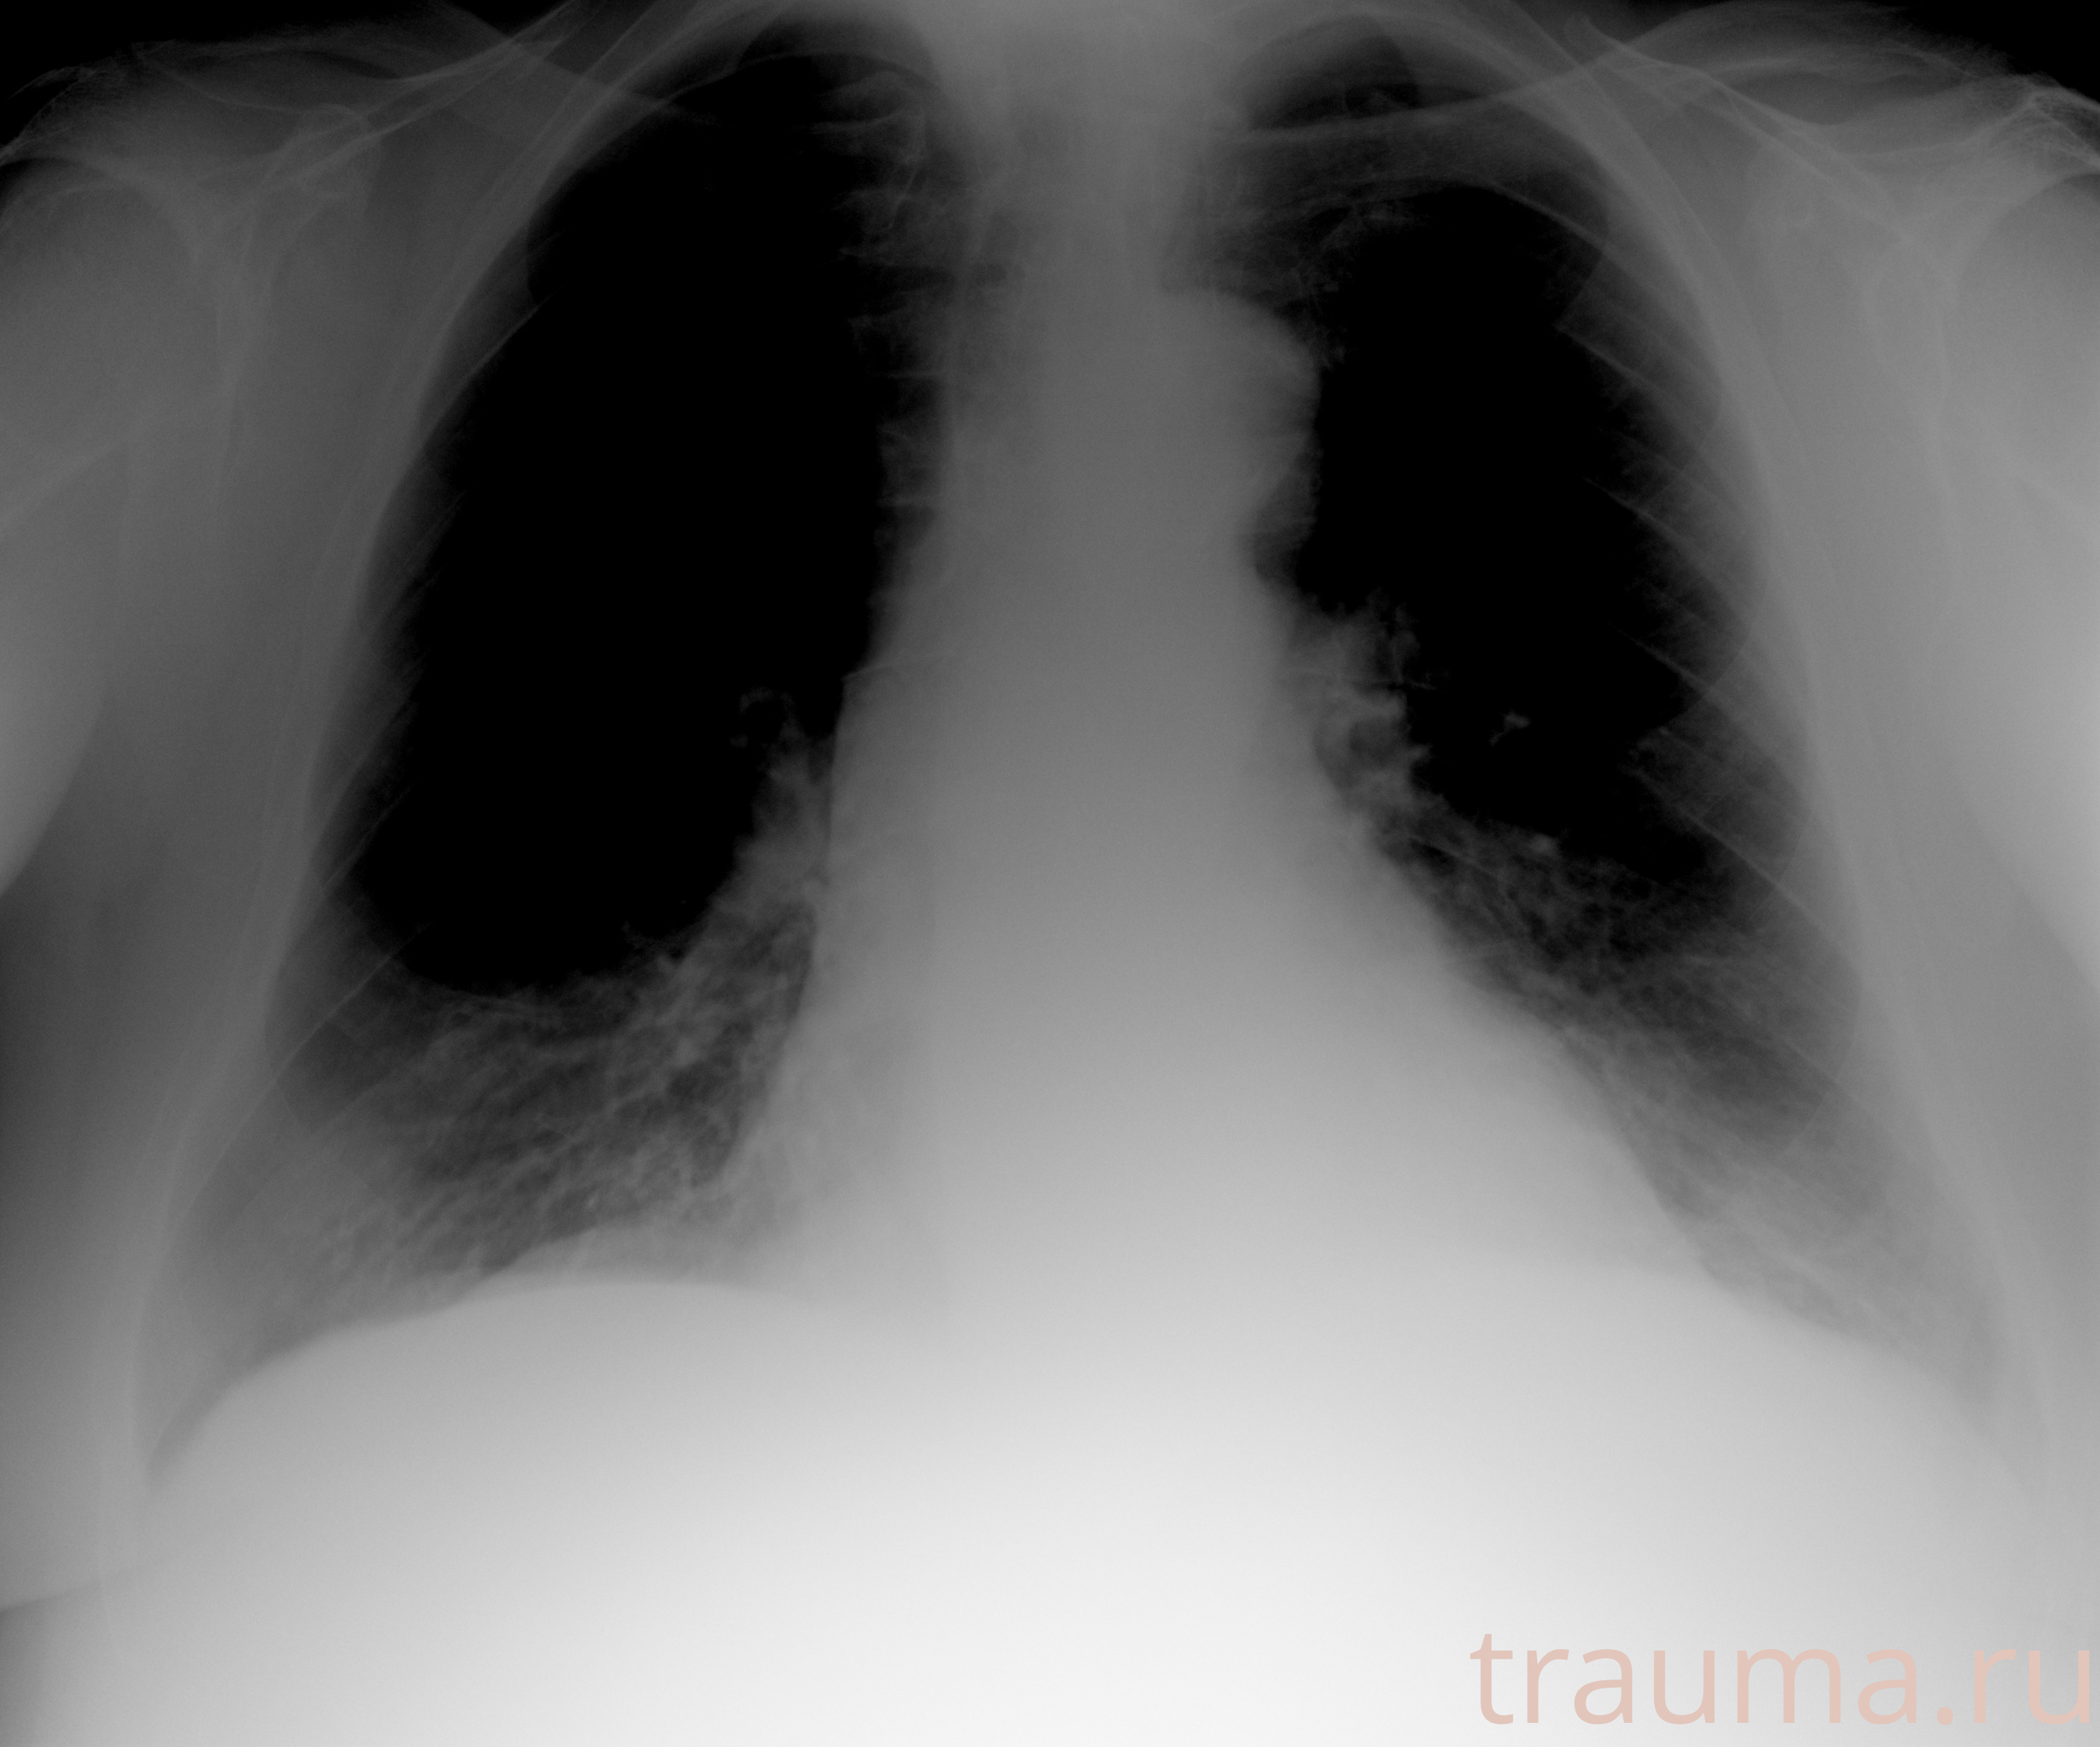

Рентгенограммы

Рентген на дому: по вашему адресу приезжает врач-рентгенолог, травматолог-ортопед с мобильным рентгеновским аппаратом, проводит диагностику травмы или заболевания, делает необходимые рентгенограммы, дает рекомендации по дальнейшему лечению. Получить качественные снимки в домашних условиях возможно благодаря уникальной методике, разработанной МосРентген Центром для института  Склифосовского

при переломе шейки бедра и пневмонии от компании МосРентген Центр - партнера Института имени Склифосовского